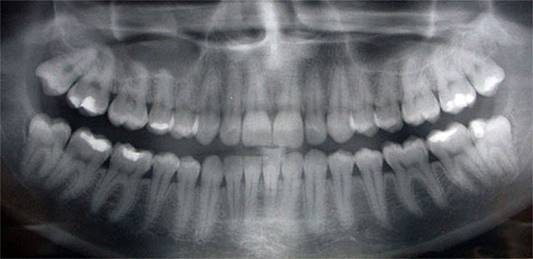

One of the key tools we use in Dental Decoding in addition to the clinical examination of the patient is the study of panoramic radiography (panoramic x-ray). We can use it to analyze several factors that are not seen with the naked eye including the shape and position of the roots of the teeth.

dientes.jpg